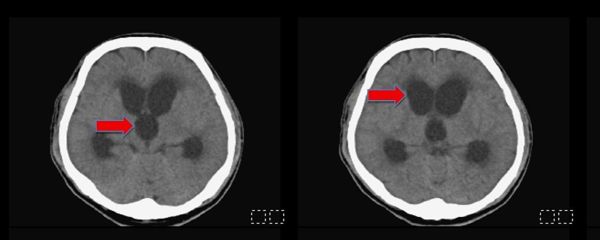

圖一、手術前腦部斷層掃描,發現所有的腦室脹大(紅色箭頭,黑色部份構造)。

圖二、手術後半年,腦部電腦斷層影像顯示,所有脹大的腦室皆已恢復正常大小,可見到所放置右側腦室的導管(紅色箭頭)。